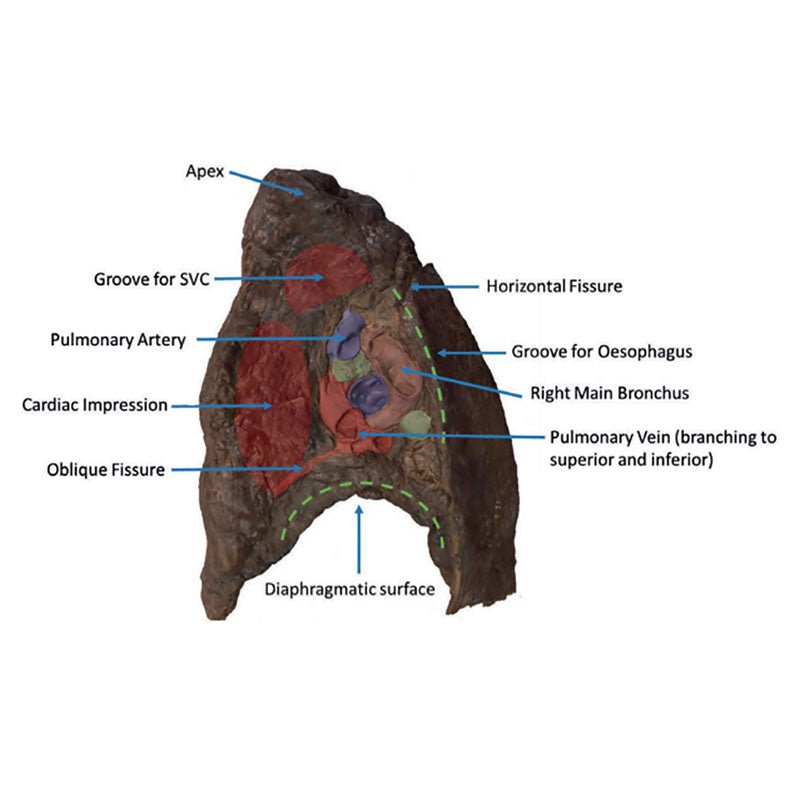

3D Printed Hilum of the Right Lung

3D Printed Hilum of the Right Lung

The hilum of a lung is the point at which visceral and parietal pleura meet and functions with the pulmonary

ligament as the lungs only connection with the rest of the body. This connection includes the Pulmonary Artery,

Superior and Inferior Pulmonary Veins, Main Bronchi, Nerves and Lymphatics.

As the definition of an artery

involves carrying blood AWAY from the heart, this will be deoxygenated blood in the pulmonary system, in

contrast with the systemic circulation. Similarly, veins carry blood TOWARDS the heart, meaning it will be

oxygenated in the pulmonary system.

With the specimen cut in a sagittal plane in line with the cardiac impression, nerves and lymphatics are difficult to identify however the groove from the oesophagus as it descends posteriorly to pierce the diaphragm can be seen alongside the cardiac impression (of the right atrium) is notable anterior to the hilum of the right lung; the right main bronchi and its subsequent divisions into lobar bronchi, found in this specimen more posterior in the hilum; he pulmonary artery and its divisions, located most superior within the hilum; the superior and inferior pulmonary veins and their divisions which are most inferior and anterior in the specimen. the oblique and horizontal fissures along the lateral surface of the specimen and the Hilar lymph nodes around the hilum on the medial surface of the lung.

The diaphragmatic surface is found inferiorly and the costal visceral surface is on the posterior of the specimen.